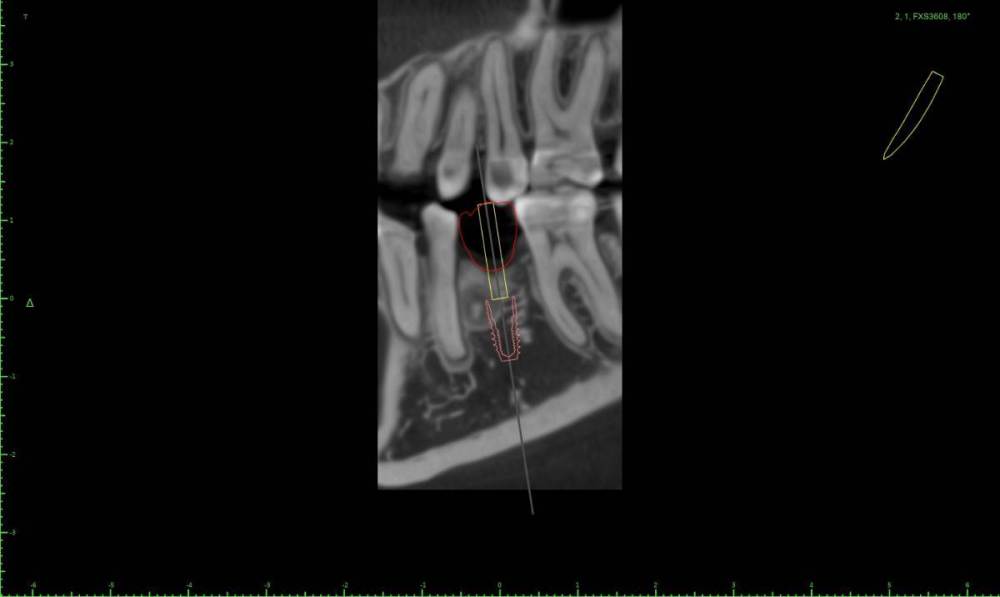

Женька Опубликовано 1 марта, 2022 Поделиться Опубликовано 1 марта, 2022 Коллеги помогайте. За качество КТ извиняйте, снимали весь череп разрешение упало у снимка. Как бы так достать его, чтобы имплантации не помешать одномоментной? Ссылка на комментарий

Irouil Опубликовано 1 марта, 2022 Поделиться Опубликовано 1 марта, 2022 Винт сместить дистальнее и чуть больше ангуляцию, примерно параллельно корням моляра соседнего судя по КТ - вестибулярно самая тонкая стенка, я бы вскрывал ее Ссылка на комментарий

Женька Опубликовано 1 марта, 2022 Автор Поделиться Опубликовано 1 марта, 2022 @Irouil тоже думал вестибулярно. Ангуляцию в сторону верхнего первого премоляра имеете ввиду? Ссылка на комментарий

Irouil Опубликовано 1 марта, 2022 Поделиться Опубликовано 1 марта, 2022 Ну да, медио-дистальную, но сохраняя выход шахты где-то в середине крестильного окна тогда в области ожидаемого дефекта кортикалки будет краешек платформы только Ссылка на комментарий